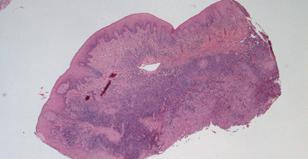

Marginal parodontitis er en plakrelateret sygdom, og plakkens sammensætning er forskellig i den supra- og den subgingivale plak. Plakken ved margo gingivae indeholder mikroorganismer, der via membranbundne komponenter og ifm. deres metabolisme

udskiller enzymer og affaldsprodukter, der påvirker sulcusepitelet og kontaktepitelet. Metabolitterne kan bl.a. være ammoniak, indol, svovlbrinte og smørsyre, der alle har en vævsskadelig effekt (6-9). Enzymerne udgøres hovedsageligt af proteaser, der er i stand til at nedbryde proteiner fra bindevævet og fra pocheekssudatet. Dette medfører en stigning i pH, da den producerede ammoniak binder H+ og herved danner ammonium. pH-stigningen medfører et øget ionprodukt og hermed øget calculusdannelse.